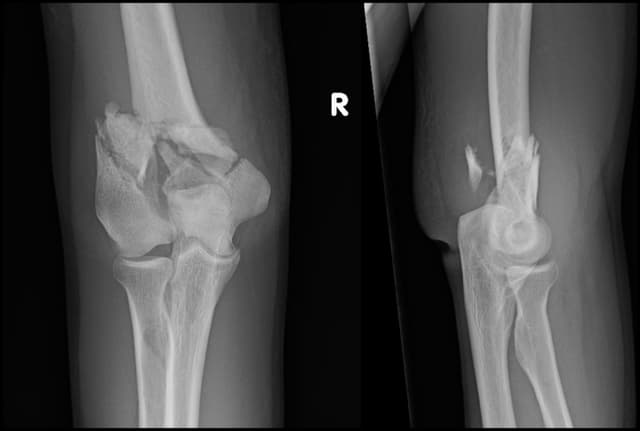

Intra-articular Distal Humerus ORIF

Pre-op